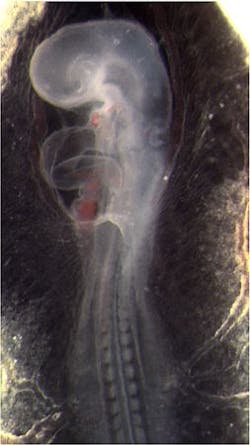

In laboratory experiments, Rollins and colleagues directly measured the heart structure and blood flow within the developing hearts of quail embryos. The data was then used to create 4D images, which showed that âlocations of high shear correspond with locations of future valve formation,â he says. âNow we are investigating the effects of abnormal shear caused by alcohol exposure on valve development.â